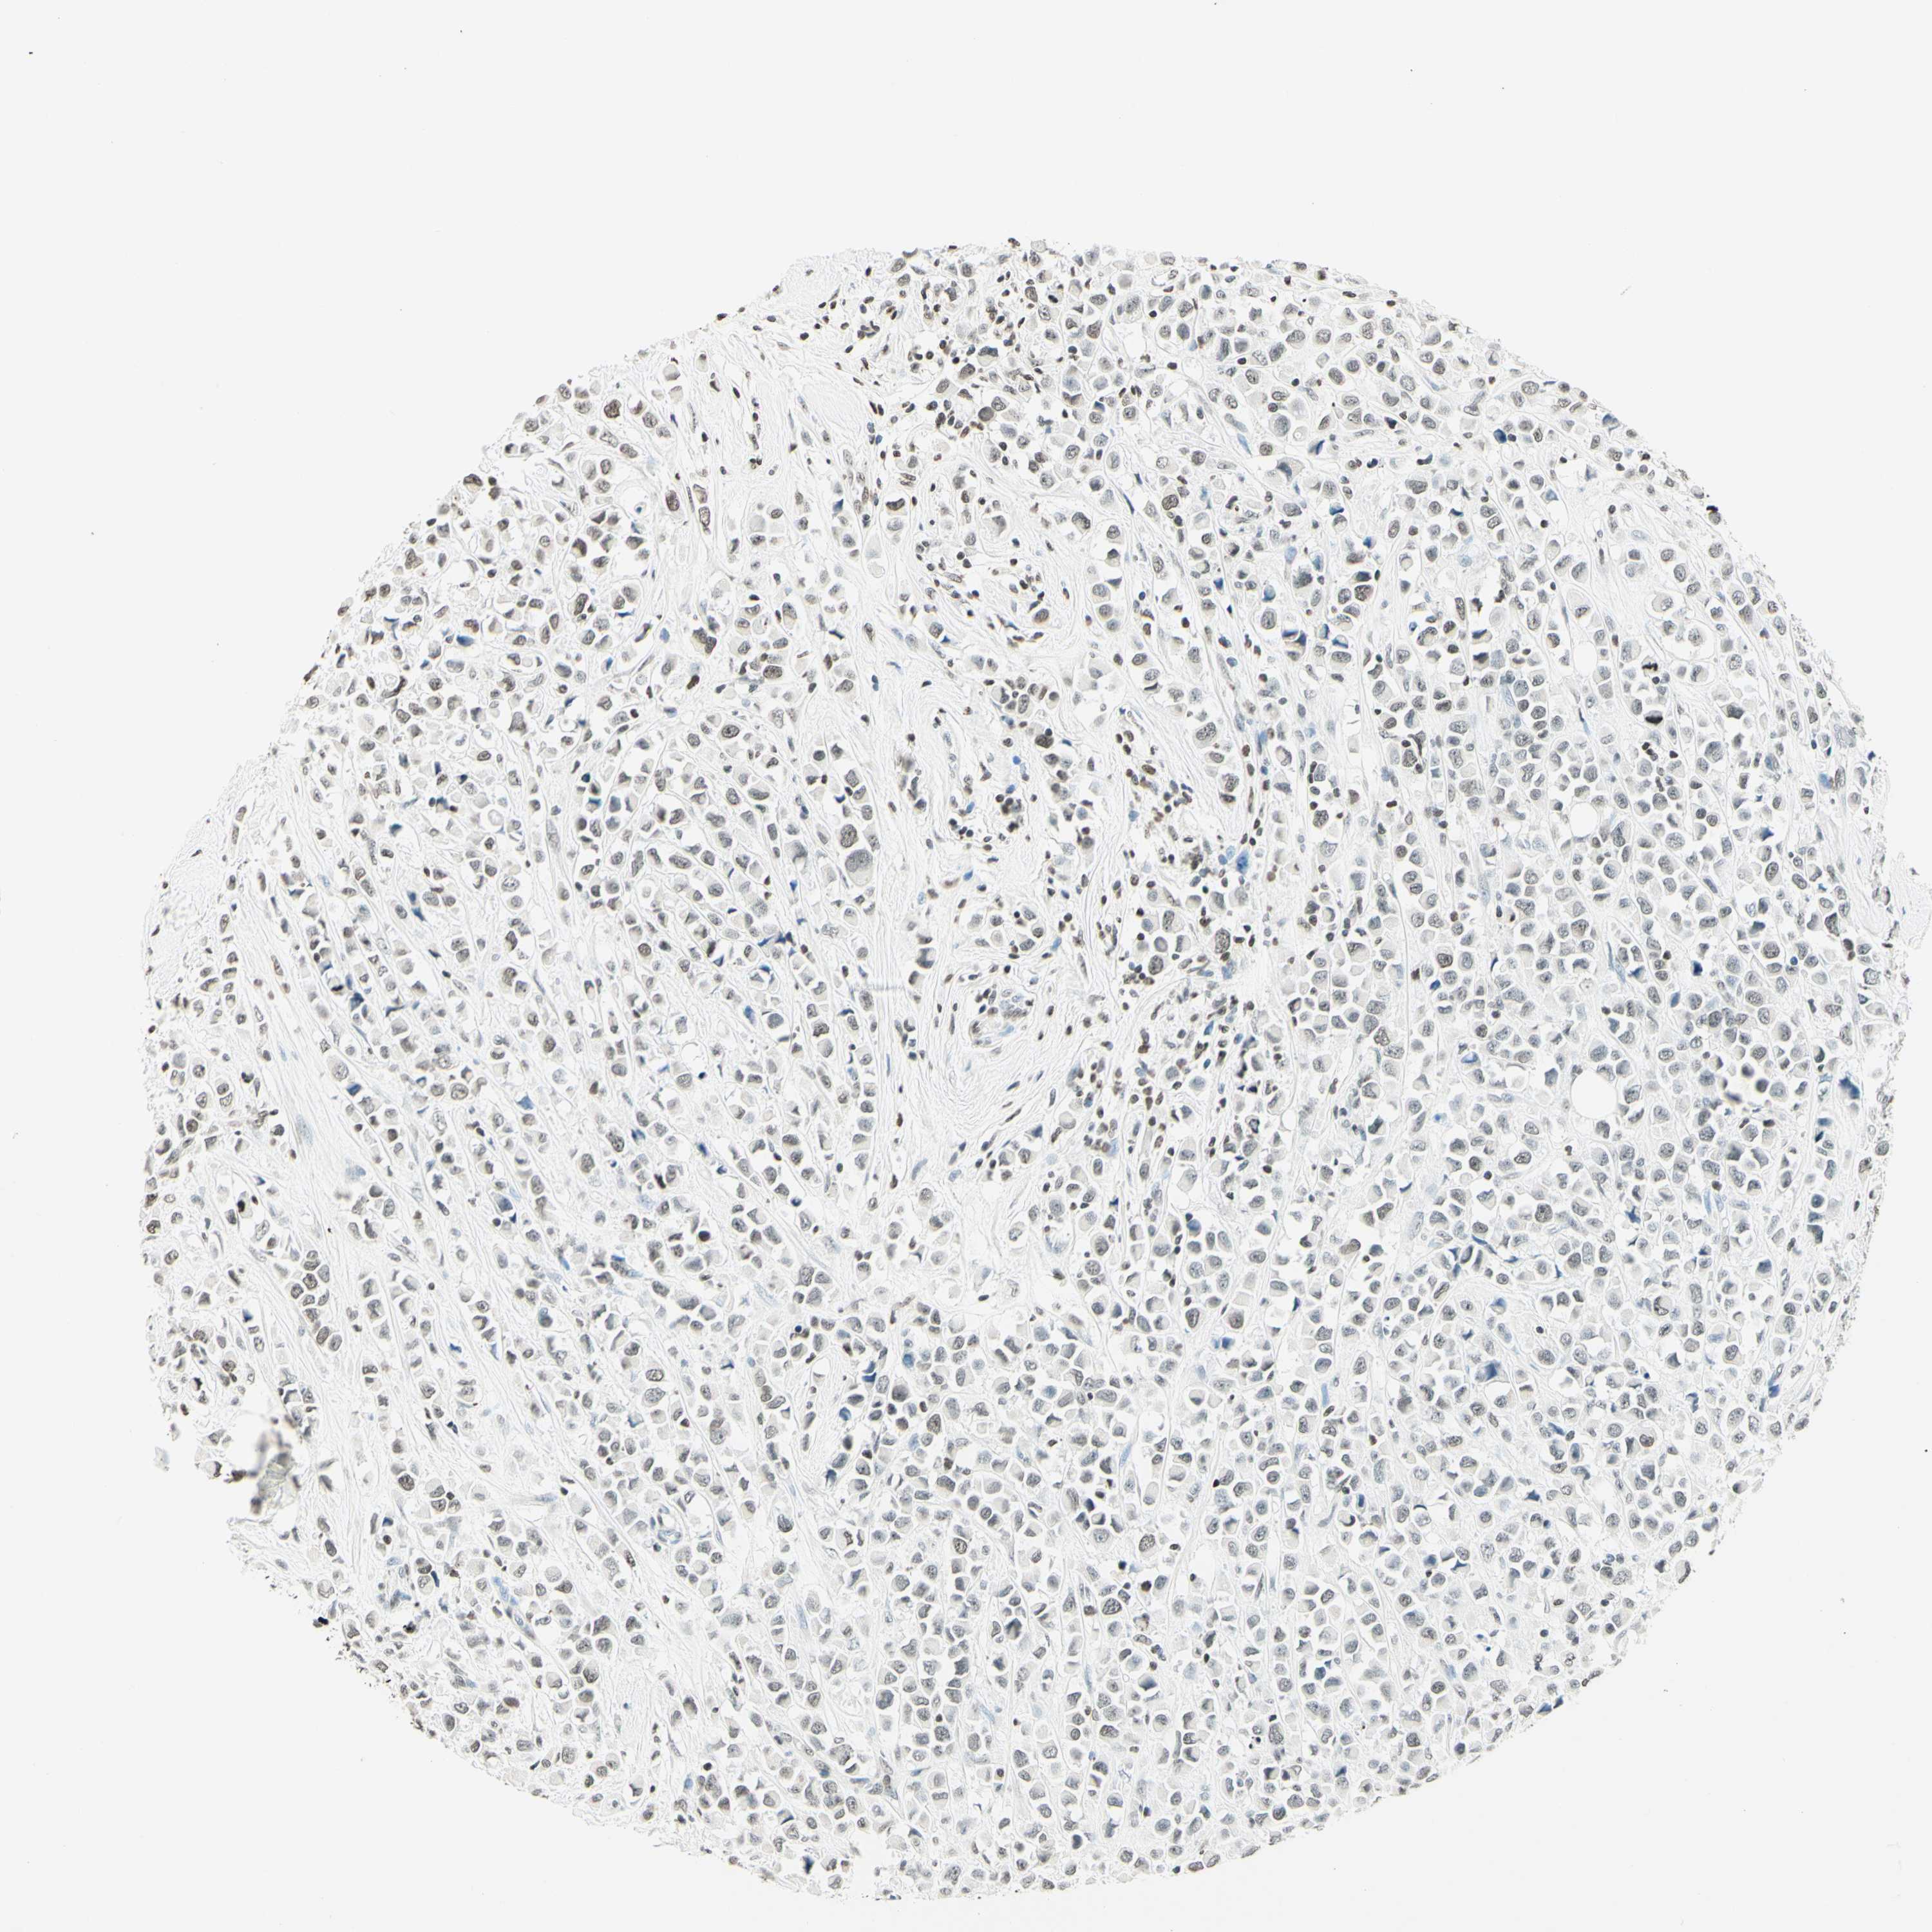

BRCA TCGA BRCA VALIDATION PROTEIN EXPRESSION